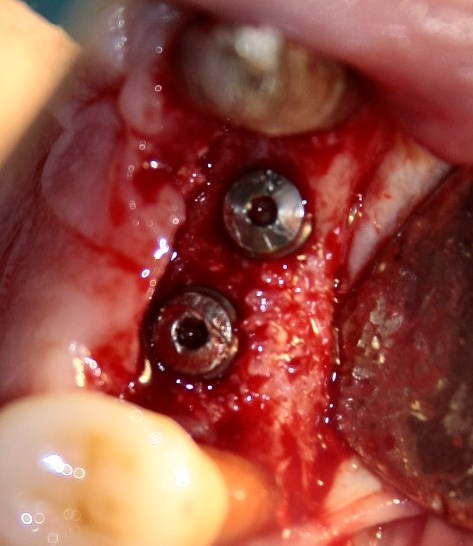

Через три месяца результат:

можно ставить формирователи и заканчивать лечение: